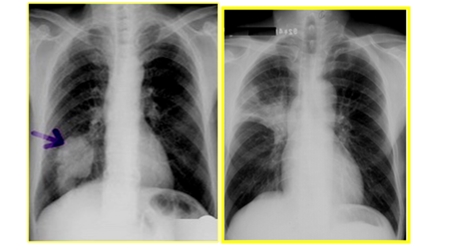

四、肺占位性病變

圖中可見肺門不規(guī)則腫塊,根據(jù)部位診斷中央型肺癌

圖中可見右下肺分葉狀腫塊,根據(jù)部位診斷周圍型肺癌

細支氣管肺泡癌

①結(jié)節(jié)型表現(xiàn)為單個的圓形陰影。

②彌漫型表現(xiàn)為兩肺彌漫分布的大小不等的結(jié)節(jié)

肺部良性與惡性腫瘤的鑒別

| 良性腫瘤 | 惡性腫瘤 | |

| 生長 | 緩慢 | 快 |

| 有無包膜 | 有 | 無 |

| 生長特點 | 對周圍組織沒有侵犯而表現(xiàn)為圓形、邊界清楚光滑的腫塊影 | 生長快、異常供血血管多,因血管進入處的阻擋導致腫塊生長呈分葉狀,因癌性淋巴結(jié)炎導致邊界短毛刺狀改變,腫瘤中心可發(fā)生缺血壞死 |